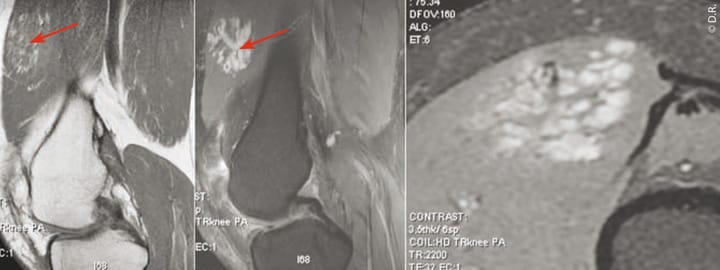

Angiome des parties molles

Pierre Le HirClinique des Lilas (93)